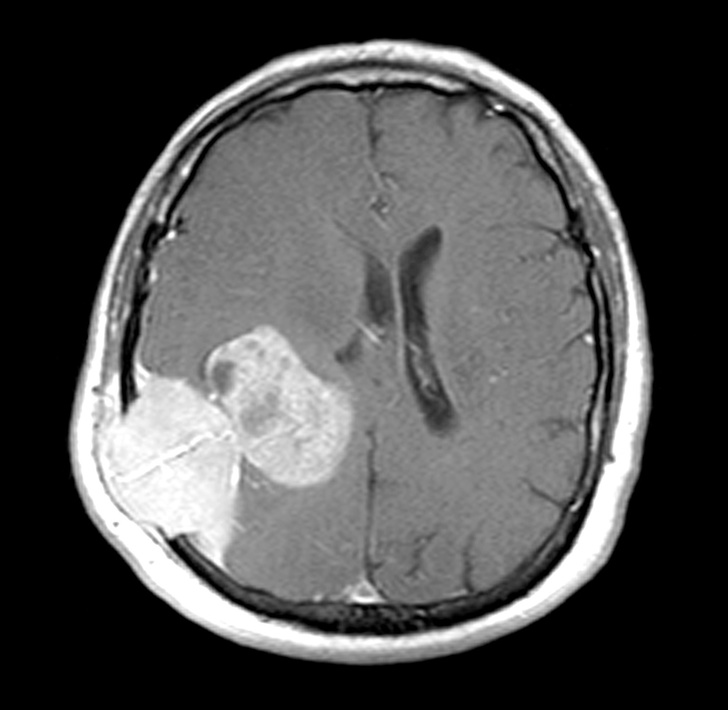

12. Пухлина мозку